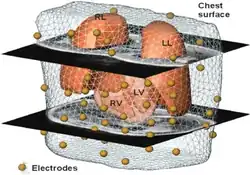

Volume Conductor Theory

Volume conductor models are a basis for source analysis in Magnetocardiography (MCG), Electrocardiography (ECG),Electroencephalography (EEG) and Magnetoencephalography (MEG). Volume conduction in bioelectromagnetism, can be defined as the transmission of electric or magnetic fields from an electric primary current source through biological tissue towards measurement sensors. Volume conductor means a continuously conductive medium.The brain, meninges, skull, and scalp make a volume conductor throughout which currents created by ionic flow can be measured.

For instance,in Electrocardiogram(ECG), it is possible to place electrodes on the body surface and measure cardiac potentials as the body behaves as a conductor of the electrical currents by the heart. In the resting, polarized state, no potential difference would exist between the positive and negative electrodes(i.e., isoelectric - flat red line). Within ventricles, when the left side of the tissue becomes depolarized (representing firing of the SA node), a wave of depolarization starts to spread across the ventricles. During this time, some part temporarily remains positive on the outside (polarized) and while some is negative (depolarized); thus, there is a separation of charges which induce a potential difference between the two electrodes. As the wave of depolarization moves toward the positive electrode, conventionally, a positive voltage (upward deflection) is recorded. The voltage reaches its maximal positive value when half the part is depolarized. Once the entire ventricle mass is depolarized (all cells negative on outside), there is no longer be a potential difference and the voltage is the same to the polarized state. When repolarization occurs, starting first with the left side ( SA nodal region) then moving across the ventricle, there will once again be both positive and negative charges on the surface of the ventricle, but this time, the negative charges will be closest to the positive electrode. The wave of repolarization sweeping across the ventricle away from the negative electrode and toward the positive electrode causes, conventionally, a negative voltage (upward deflection in ventricles. It is different according to the part.) to occur. Finally, when all of the cells are repolarized, the measured voltage difference will once again be the same to the initial stage until another wave of depolarization occurs.

The Human Body as a Volume Conductor

The human body would be thought as a resistive, piecewise homogeneous and linear volume conductor. Most of the tissue is isotropic. The muscle is, however, strongly anisotropic, and the brain tissue is anisotropic,too.